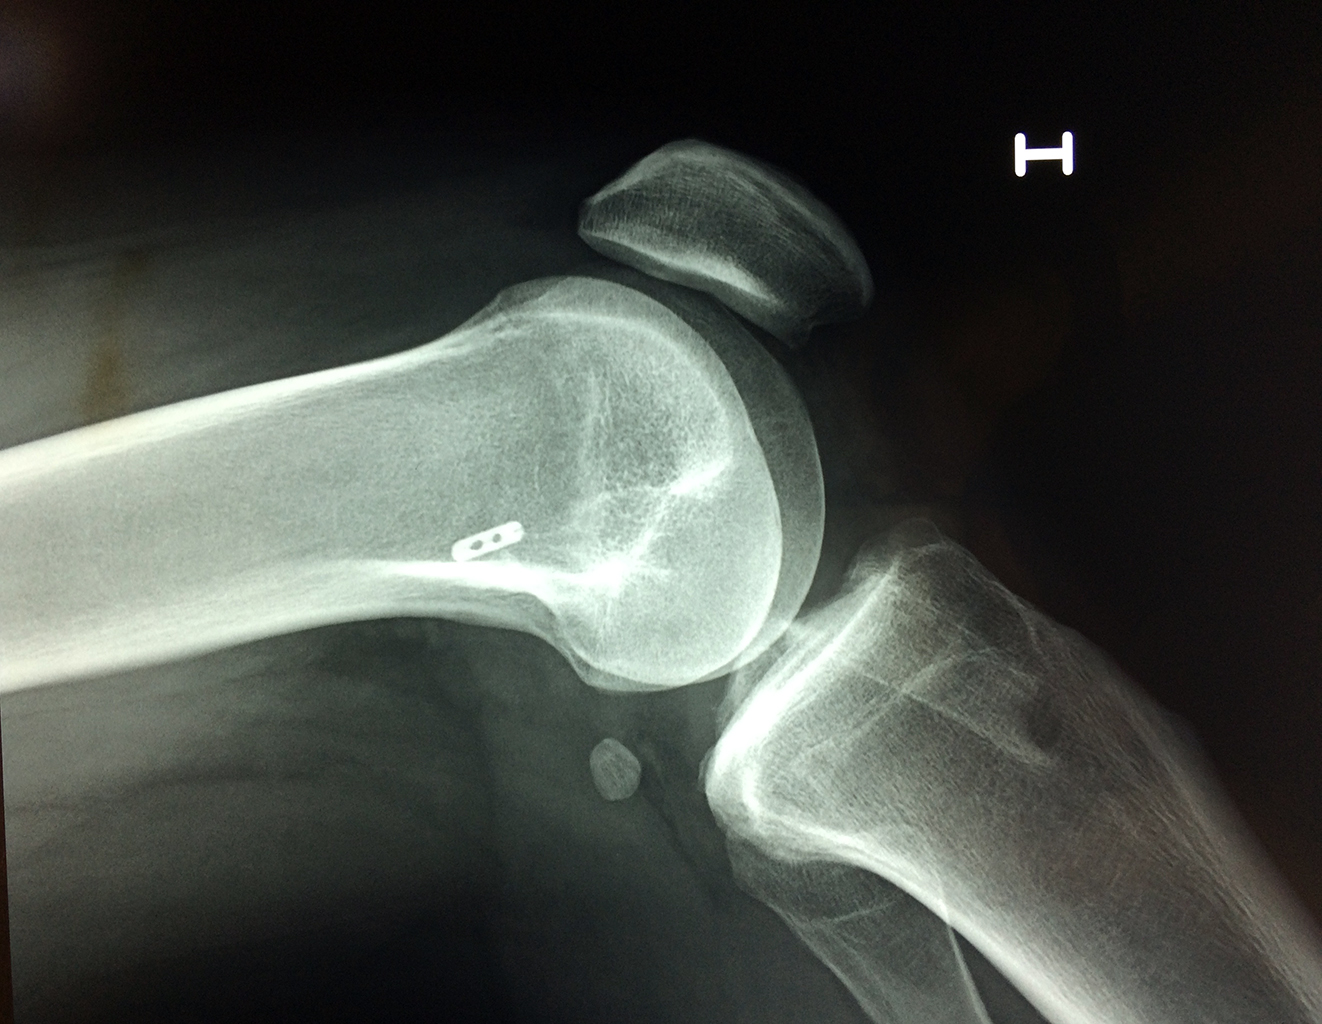

La artroscopia de rodilla es un cirugía en el cual la estructura interna de la articulación es examinada ya sea para realizar un diagnostico o para realizar un tratamiento, este procedimiento se realiza utilizando un instrumento parecido a un pequeño tubo llamado artroscopio.